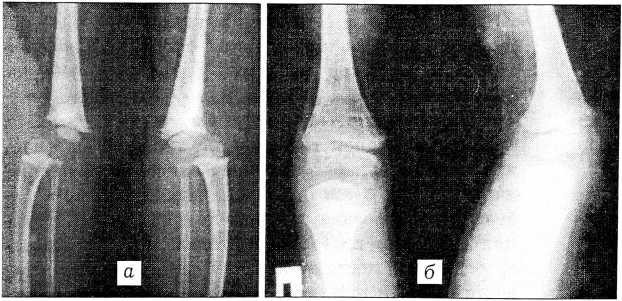

Рис. 3. Рентгенограммы больного с синдромом Ларсен. а — передние вывихи обеих голеней; б — нормальные соотношения в коленных суставах через 16 мес после открытого вправления вывихов голеней.

Следующий этап — вправление вывиха голеней одномоментно под наркозом с последующей фиксацией спицами и гипсовыми лонгетами в течение 3- 4 нед. После удаления спиц накладываются циркулярные гипсовые повязки на срок до 4 мес. Таким способом вывихи были устранены у 8 пациентов. При неудаче вправления вывиха голеней под наркозом не следует предпринимать повторных попыток, которые часто не дают желаемого результата, сопровождаются глубокой травматизацией мышечносвязочного аппарата и сопряжены со значительным риском перелома бедра. Так, под нашим наблюдением находился ребенок с неправильно сросшимся переломом нижней трети бедренной кости, явившимся следствием неоднократных попыток вправления вывиха голеней в возрасте 2 мес. Применение аппарата Илизарова для вправления вывиха голеней (2 пациента) не увенчалось успехом. Наш опыт показал, что иногда в наиболее тяжелых случаях синдрома Ларсен дистальный отдел четырехглавой мышцы бедра представляет собой соединительнотканный тяж, препятствующий вправлению. При подтверждении этого электрофизиологическими исследованиями целесообразно сразу же — без попыток закрытого вправления — произвести открытое вправление вывиха голеней с удлинением мышц-разгибателей и трансартикулярной фиксацией коленного сустава спицами Киршнера. Операция выполняется из переднего доступа типа Пайра, двумя бригадами хирургов сразу на обеих конечностях. Гипсовая иммобилизация осуществляется в течение 4-5 мес. Подобные вмешательства выполнены у 2 детей в возрасте 8 мес и 2,5 лет (рис. 3).